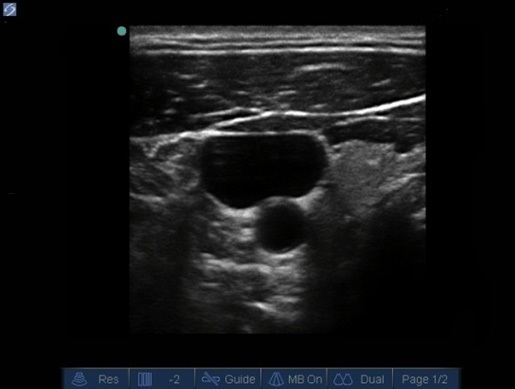

Ajuste de profundidad - Imagen óptima